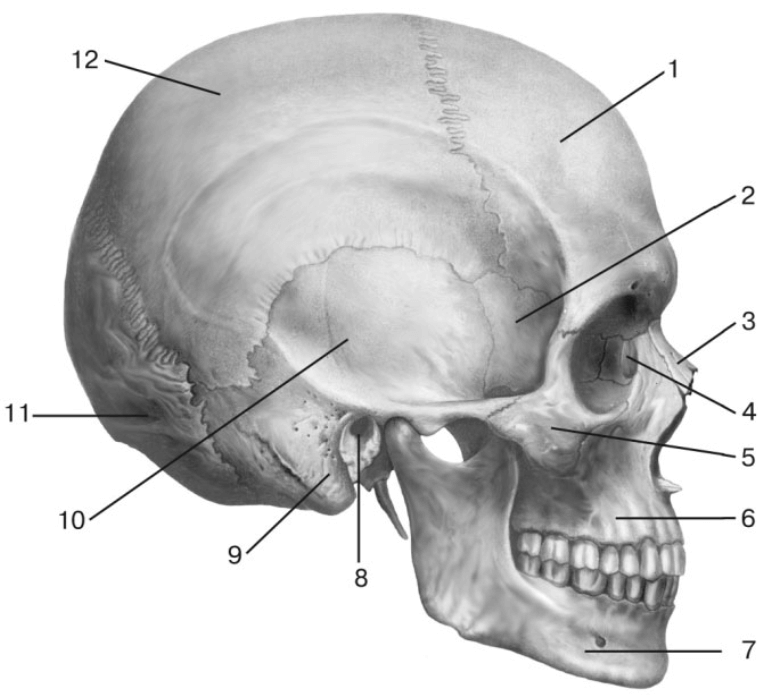

Анатомия детского черепа: Рентгеновские снимки и описание